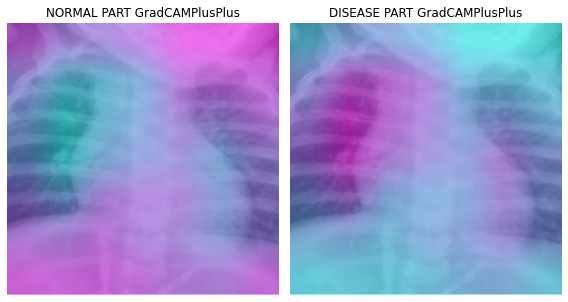

fig, (ax1,ax2) = plt.subplots(1,2)

dls.train.decode((x,))[0].squeeze().show(ax=ax1)

ax1.imshow(-cam_gradcamplusplus.squeeze(),alpha=0.5,extent=(0,224,224,0),interpolation='bilinear',cmap='cool')

ax1.set_title("NORMAL PART GradCAMPlusPlus")

#

dls.train.decode((x,))[0].squeeze().show(ax=ax2)

ax2.imshow(cam_gradcamplusplus.squeeze(),alpha=0.5,extent=(0,224,224,0),interpolation='bilinear',cmap='cool')

ax2.set_title("DISEASE PART GradCAMPlusPlus")

fig.set_figwidth(8)

fig.set_figheight(8)

fig.tight_layout()